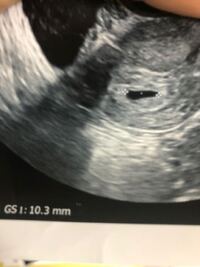

こんばんは 今日ちょうど7週になる妊婦です このエコーに血の塊は見え Yahoo 知恵袋